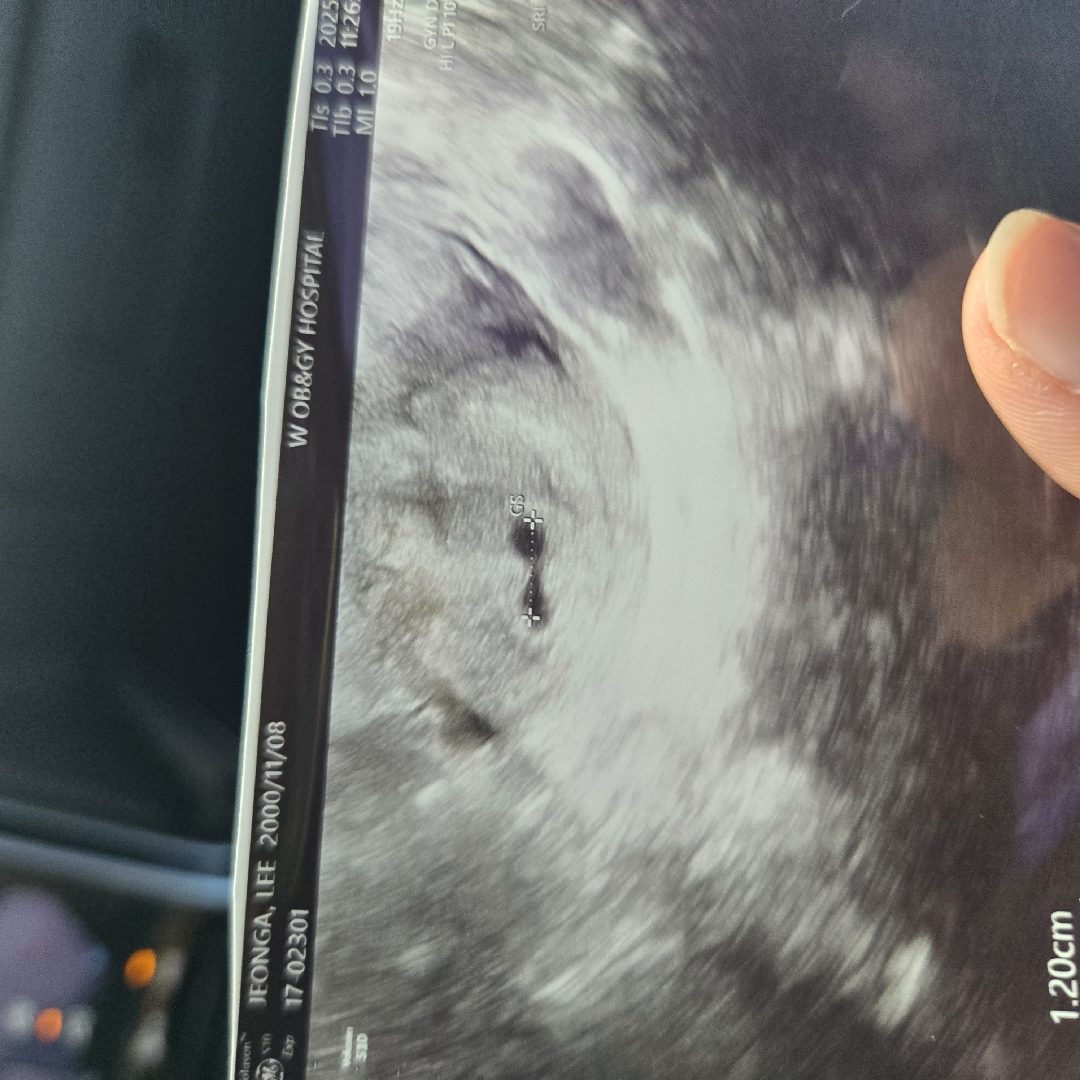

GS는 아기집이에요! 다음주면 심장소리는 아니여도 난황은 보러 가실수 있구용 7주차전에 심장소리 들으면되용 !

저번주 5주2일째갔는데요 태아크기 1,20cm 래요 내일심장소리들으러오랬는데 들리겠죠?

억 저 2주 전에 갔을때 5주 3일 아가집이 0.66cm 였어요 저는 배아 크기 못쟀는데 배아가 1.2센치나 됏어요?

저기 GS라 적힌건 배아가 아니라 아기집 크기 같아요!

아직난황이랑은안보였어요